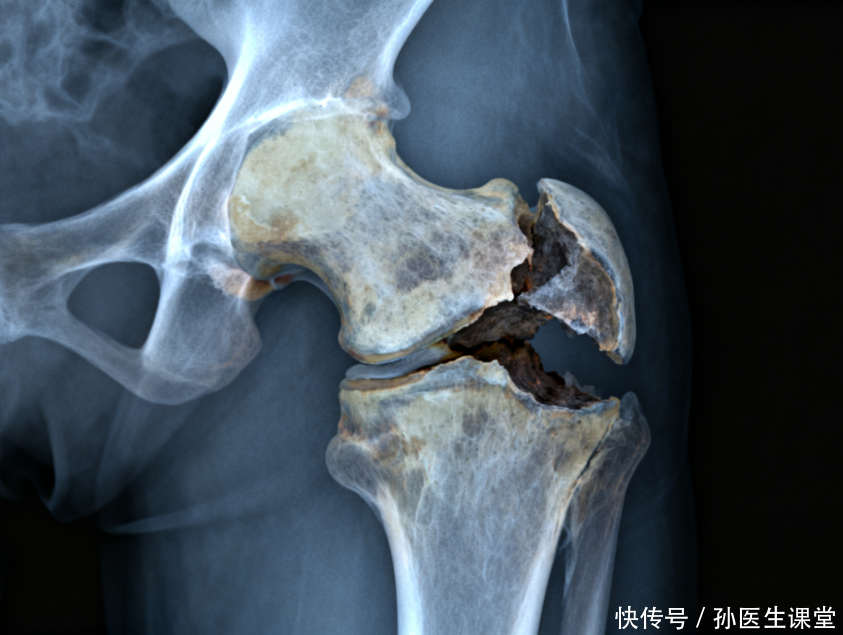

很多人对“股骨头坏死”这五个字充满误解。它并不是突然“断掉”的骨头,而是股骨头内部的骨小梁因为长期供血不足而逐步失去活性,像一座被抽走支柱的拱顶,早期外观尚可,负重久了便慢慢变形、塌陷。髋关节承担着站立与行走的全部重量,问题一旦出现,生活质量会明显下滑。

如何确诊?体格检查能提供方向,但关键在影像学。普通X线在早期可能显示正常或只有细微改变,核磁共振(MRI)对早期病变更敏感,能在X线“看不见”的阶段发现骨内信号异常。必要时,结合CT评估骨结构。分期很重要,因为不同阶段的处理策略差异明显。